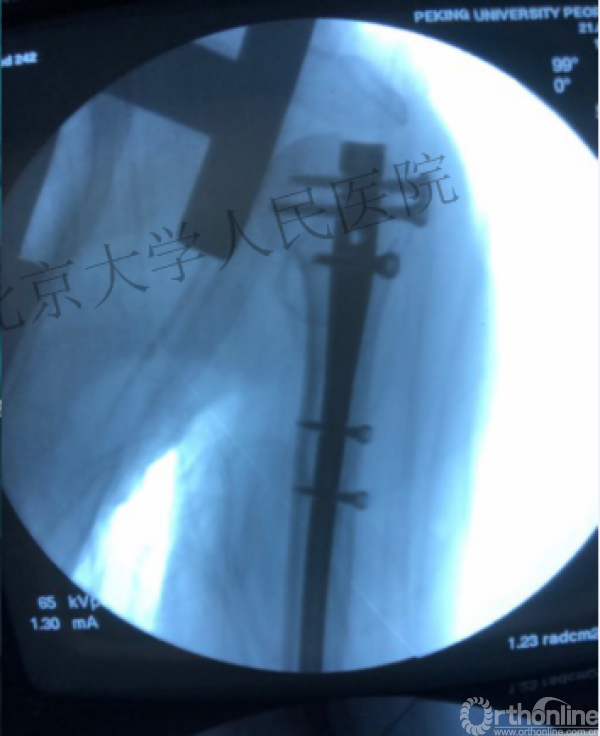

复位良好的标准:颈干角:135°,大结节与肱骨头距离:8mm

术后3月随访:继发性颈干角变小22°(5-82),肱骨头内翻,达46%

严重影响了患者的生活质量

术中片